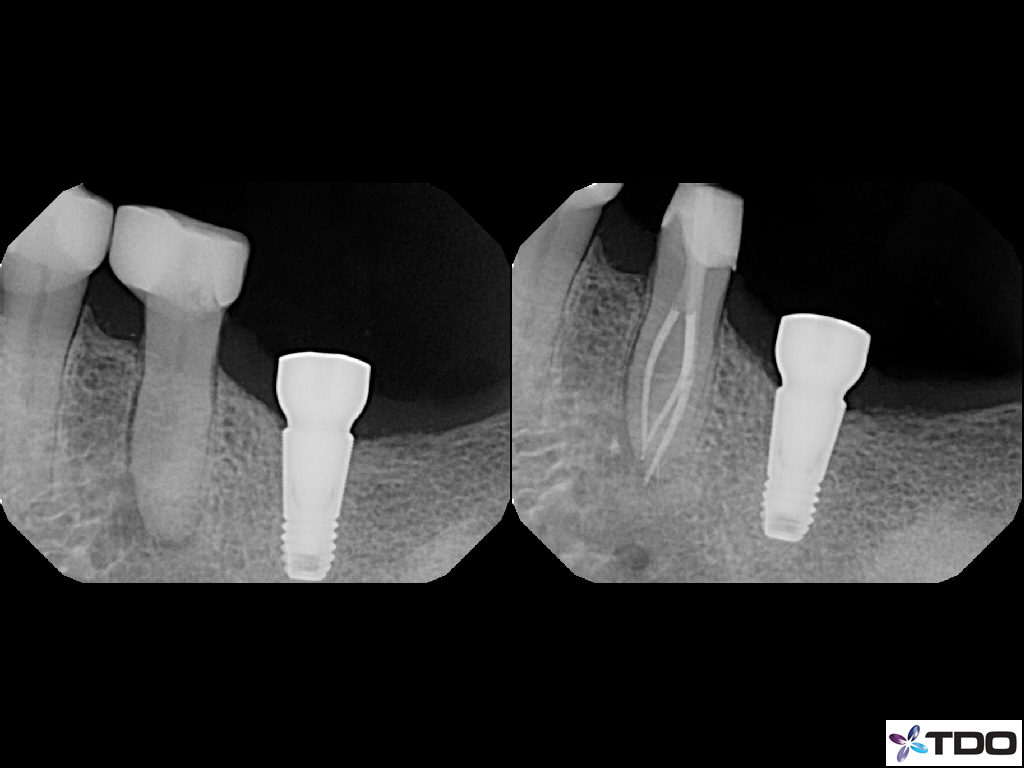

These cases show a level of commitment to conservative endodontics rarely seen in endo today. Plus the restorative excellence is inspiring and should stimulate all endodontists to up their game and help others realize how important the restorative aspect of endodontics is.